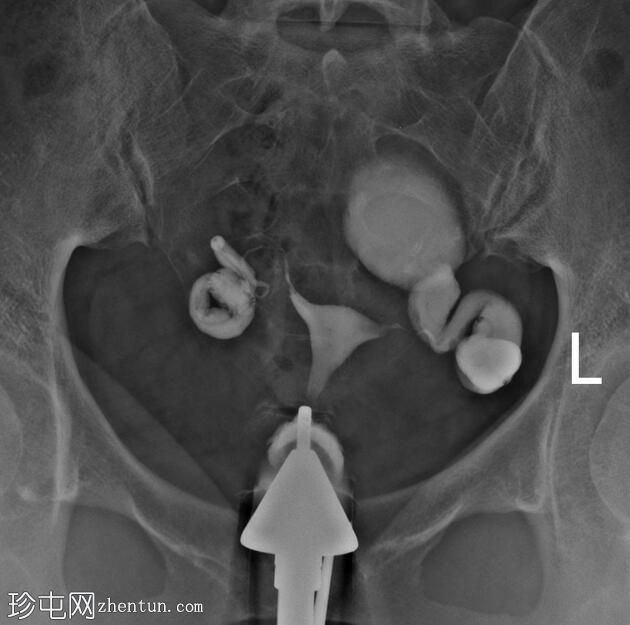

右侧输卵管扩张并充满液体,无腹膜溢出,提示输卵管积水及输卵管阻塞。

左侧输卵管亦扩张并充满液体,伴有造影剂残留及少量溢出,提示输卵管积水及输卵管阻塞。

此外,左侧盆腔内,位于输卵管上内侧,可见大量分隔的造影剂积聚,并伴有盆腔输卵管周围粘连。